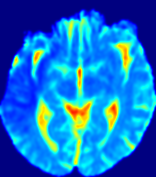

4.3.2 Diffusion Imaging via Advection-Diffusion

Slice #1Slice #2Slice #3Slice #4Slice #5Slice #6Dgtsuperscript𝐷gtD^{\text{gt}}Refer to captionRefer to captionRefer to captionRefer to captionRefer to captionRefer to captionDestsuperscript𝐷estD^{\text{est}}Refer to captionRefer to captionRefer to captionRefer to captionRefer to captionRefer to captionRefer to caption0.300.300.300.240.240.240.180.180.180.120.120.120.060.060.060.000.000.00(mm2/s)𝑚superscript𝑚2𝑠(mm^{2}/s)𝐕est𝟐subscriptnormsuperscript𝐕est2\|\bf{V}^{\text{est}}\|_{2}Refer to captionRefer to captionRefer to captionRefer to captionRefer to captionRefer to captionRefer to caption0.00300.00300.00300.00240.00240.00240.00180.00180.00180.00120.00120.00120.00060.00060.00060.00000.00000.0000(mm/s)𝑚𝑚𝑠(mm/s)

Figure 15: PIANO identifiability testing: diffusion imaging via advection-diffusion. Top row shows Dgtsuperscript𝐷gtD^{\text{gt}} used for simulating ground truth pure diffusion. Rows below show the estimated Destsuperscript𝐷estD^{\text{est}} and 𝐕est2subscriptnormsuperscript𝐕est2\|{\bf{V}}^{\text{est}}\|_{2} on corresponding slices. Note that the plotted value scale for 𝐕est2subscriptnormsuperscript𝐕est2\|{\bf{V}}^{\text{est}}\|_{2} is 0.01 of that for Dgtsuperscript𝐷gtD^{\text{gt}} and Destsuperscript𝐷estD^{\text{est}}.

Similarly, we test the behavior of PIANO when estimating both advection and diffusion from a pure diffusion-driven process. The goal is to determine if PIANO is able to recognize that there is only diffusion governing the given concentration time-series. We use the same ‘Diffusion Imaging’ data simulation of Sec. 4.2.1 as the concentration dataset, PIANO estimates both velocity 𝐕estsuperscript𝐕est{\bf{V}}^{\text{est}} and diffusivity Destsuperscript𝐷estD^{\text{est}}. Estimation results in Fig. 15 confirm PIANO’s identifiability again: the estimated 𝐕est2subscriptnormsuperscript𝐕est2\|{\bf{V}}^{\text{est}}\|_{2} is almost invisible compared to Destsuperscript𝐷estD^{\text{est}}, even plotted with a 1%percent11\% value range compared to that for Destsuperscript𝐷estD^{\text{est}}. On the other hand, Destsuperscript𝐷estD^{\text{est}} achieves comparable estimation performance as ‘Diffusion Imaging via Diffusion’ in which PIANO predicts Destsuperscript𝐷estD^{\text{est}} alone (shown in Fig. 13).